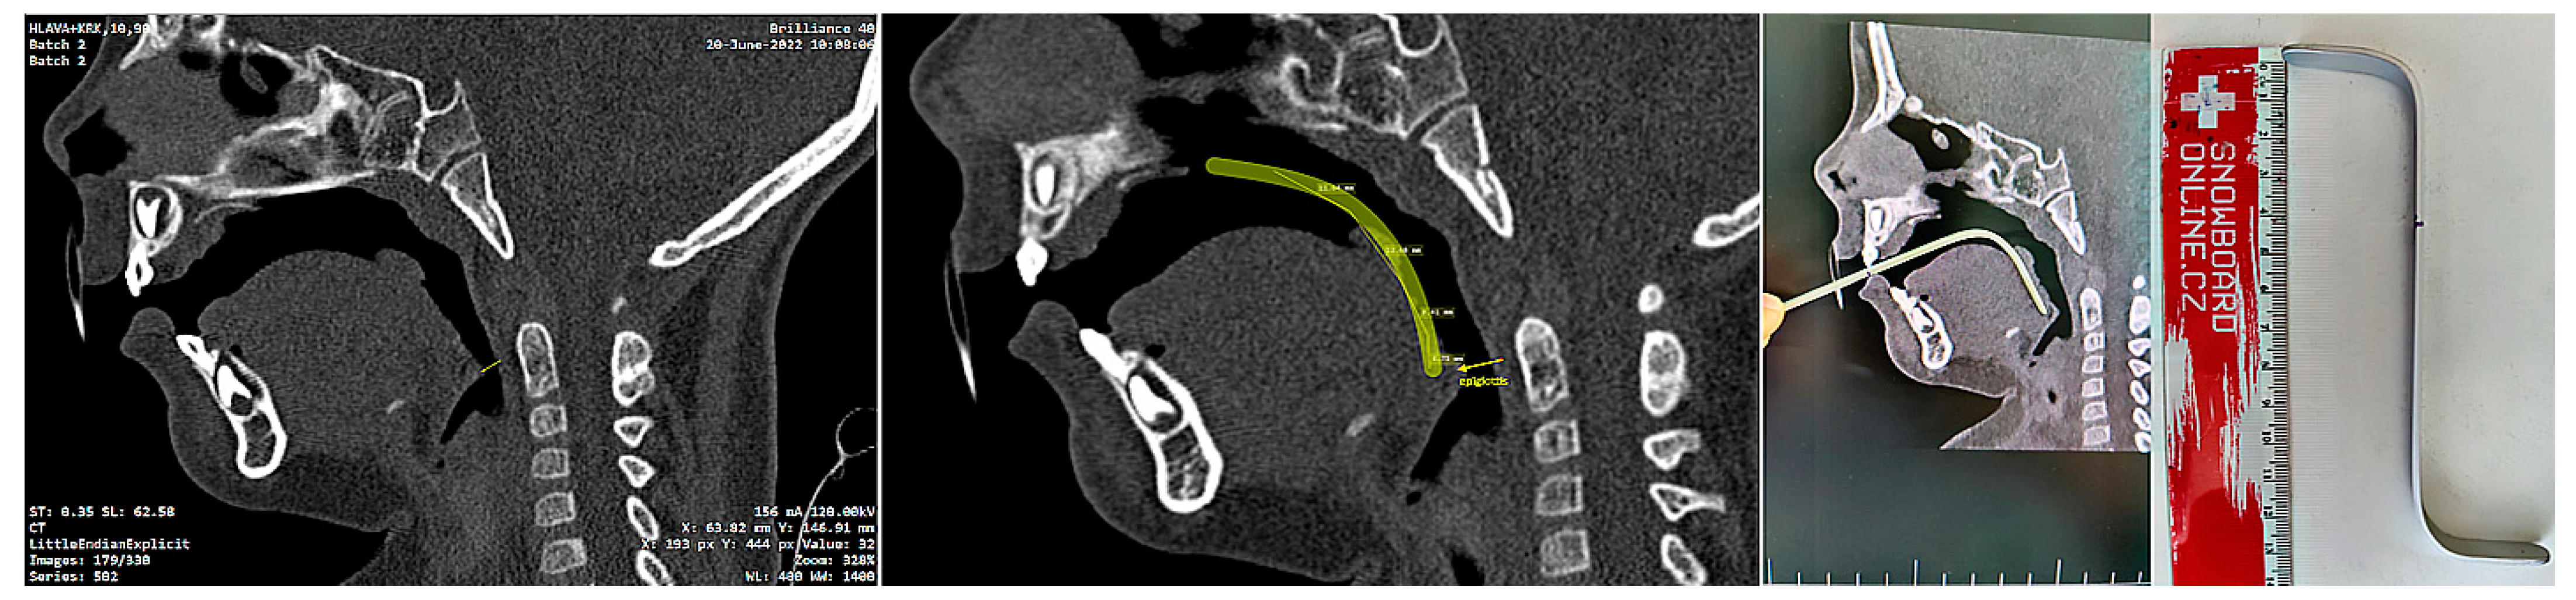

The invasiveness of the presented concept lies in the necessity of the initial CT scan, albeit some experts do not consider x-ray examination as an invasive examination method. CT uses ionizing radiation that may cause damage to DNA, and children are at greater risk of carcinogenesis due to their higher tissue radiosensitivity and their longer life expectancy compared to adults. The costs and benefits of the examination for the patient must be clear. In life-threatening situations involving severe craniofacial syndromes, a CBCT or CT scan is performed working from other indications. Figure 7. shows the intention of pediatric otorhinolaryngology department to provide orthodontists with a guide for the approximate ideal length of the spur, visualized on the sagittal slice of the CT scan (Figure 7). The method presented in this paper provides information about 3D patient virtualization. The airway entry with the spur must recognize not only a potential maxillary cant, but also any asymmetries or lateral excursions of the airway where the spur will be oriented. A majority of these can be evaluated without the necessity of CBCT/CT diagnostics. This paper does not define 3D x-ray examination as a necessity. The described method enables 3D design based on segmented CT or CBCT scan.

Segmentation of the airway in the area between the nasopharynx and oropharynx is important to plan the spur’s position, especially in craniofacial syndromes with palatal cleft. Figure 8 shows a CT image of the segmented airway showing the complete morphology from the epiglottis up to the nasopharynx.